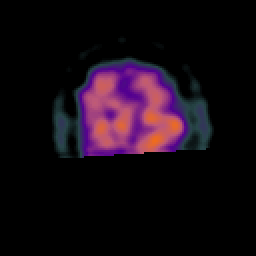

Subacute Stroke, overlay -- Slice #22

[Home][Help][Clinical] Slice 22